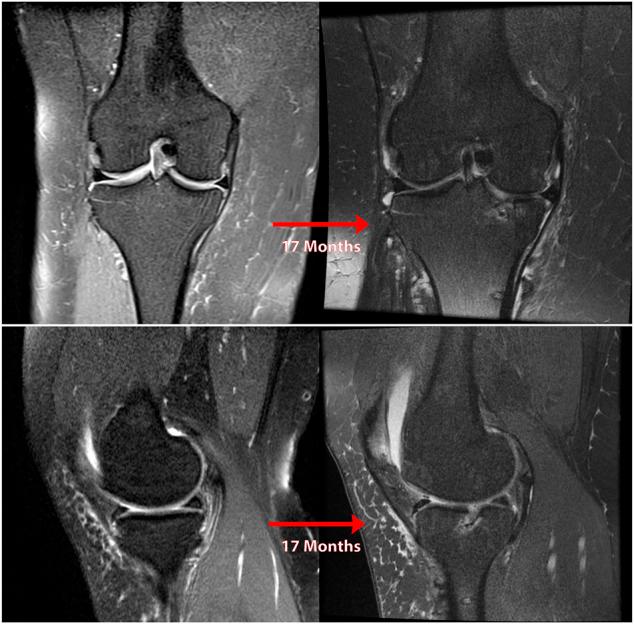

Posterior medial meniscus root tears (PMMRTs) make up a relatively notable proportion of all meniscus pathology and have been definitively linked to the progression of osteoarthritis (OA). While known risk factors for development of OA in the knee include abnormal tibial coronal alignment, obesity and female gender, PMMRTs have emerged in recent years as another significant driver of degenerative disease. These injuries lead to an increase in average contact pressure in the medial compartment, along with increases in peak contact pressure and a decrease in contact area relative to the intact state. Loss of the root attachment impairs the function of the entire meniscus and leads to meniscal extrusion, thus impairing the force-dissipating role of the meniscus. Anatomic meniscus root repairs with a transtibial pullout technique have been shown biomechanically to restore mean and peak contact pressures in the medial compartment. However, nonanatomic root repairs have been reported to be ineffective at restoring joint pressures back to normal. Meniscal extrusion is often a consequence of nonanatomic repair and is correlated with progression of OA. In this study, the authors will describe the biomechanical basis of the natural history of medial meniscal root tears and will support the biomechanical studies with a case series including patients that either underwent non-operative treatment (5 patients) or non-anatomic repair of their medial meniscal root tears (6 patients). Using measurements derived from axial MRI, the authors will detail the distance from native root attachment center of the non-anatomic tunnels and discuss the ongoing symptoms of those patients. Imaging and OA progression among patients who were treated nonoperatively before presentation to the authors will be discussed as well. The case series thus presented will illustrate the natural history of meniscal root tears, the consequences of non-anatomic repair, and the findings of symptomatic meniscal extrusion associated with a non-anatomic repair position of the meniscus.

后内侧半月板根部撕裂(PMMRTs)在所有半月板病变中占比较显著,并且已明确与骨关节炎(OA)的进展相关。虽然已知膝关节OA发展的风险因素包括胫骨冠状面排列异常、肥胖和女性性别,但近年来PMMRTs已成为退行性疾病的另一个重要驱动因素。这些损伤导致内侧间室平均接触压力增加,同时峰值接触压力增加,且相对于完整状态接触面积减小。根部附着的丧失会损害整个半月板的功能,并导致半月板挤出,从而损害半月板的力消散作用。经胫骨拉出技术进行的解剖学半月板根部修复在生物力学上已显示可恢复内侧间室的平均和峰值接触压力。然而,据报道非解剖学根部修复在将关节压力恢复到正常水平方面无效。半月板挤出通常是非解剖学修复的结果,并且与OA的进展相关。在本研究中,作者将描述内侧半月板根部撕裂自然病程的生物力学基础,并将通过一个病例系列来支持生物力学研究,该病例系列包括接受非手术治疗的患者(5例)或内侧半月板根部撕裂接受非解剖学修复的患者(6例)。作者将使用从轴向MRI得出的测量值,详细说明非解剖学隧道与天然根部附着中心的距离,并讨论这些患者的持续症状。还将讨论在向作者就诊之前接受非手术治疗的患者的影像学和OA进展情况。因此呈现的病例系列将说明半月板根部撕裂的自然病程、非解剖学修复的后果以及与半月板非解剖学修复位置相关的有症状半月板挤出的发现。